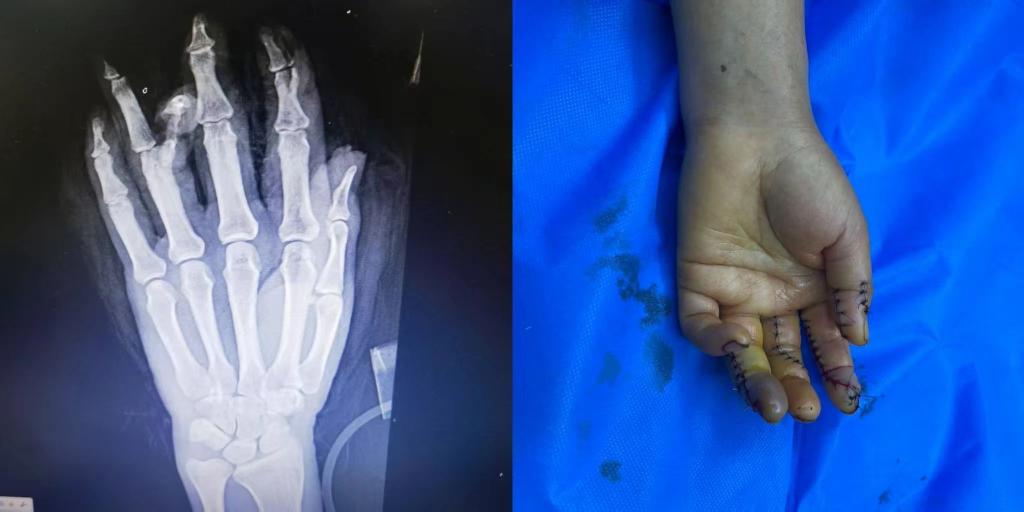

5月1日下午15点30分,beat365中文在线官网第五临床医学院2020级临床医学班的学生小马(化名)接到了来自伊犁亲戚的电话。电话中得知,亲戚在工作中不幸遭遇意外,左手被机器压伤,导致拇指、食指、中指、无名指均受到不同程度的损伤,受伤最严重的是食指和无名指,竖向劈开了骨头。由于多指多段离断的严重毁损伤,手术难度很大,当地医院的条件有限,为保住患者手指,需要申请前往上级医疗机构治疗。

随后,患者被送入手术室,由李华医生主刀,进行了长达7个小时的断指再植手术。

术后患者损伤严重的手恢复了基本形态,手指末梢血液循环逐步恢复。目前患者的情况基本平稳,在医院等待进一步观察和恢复。